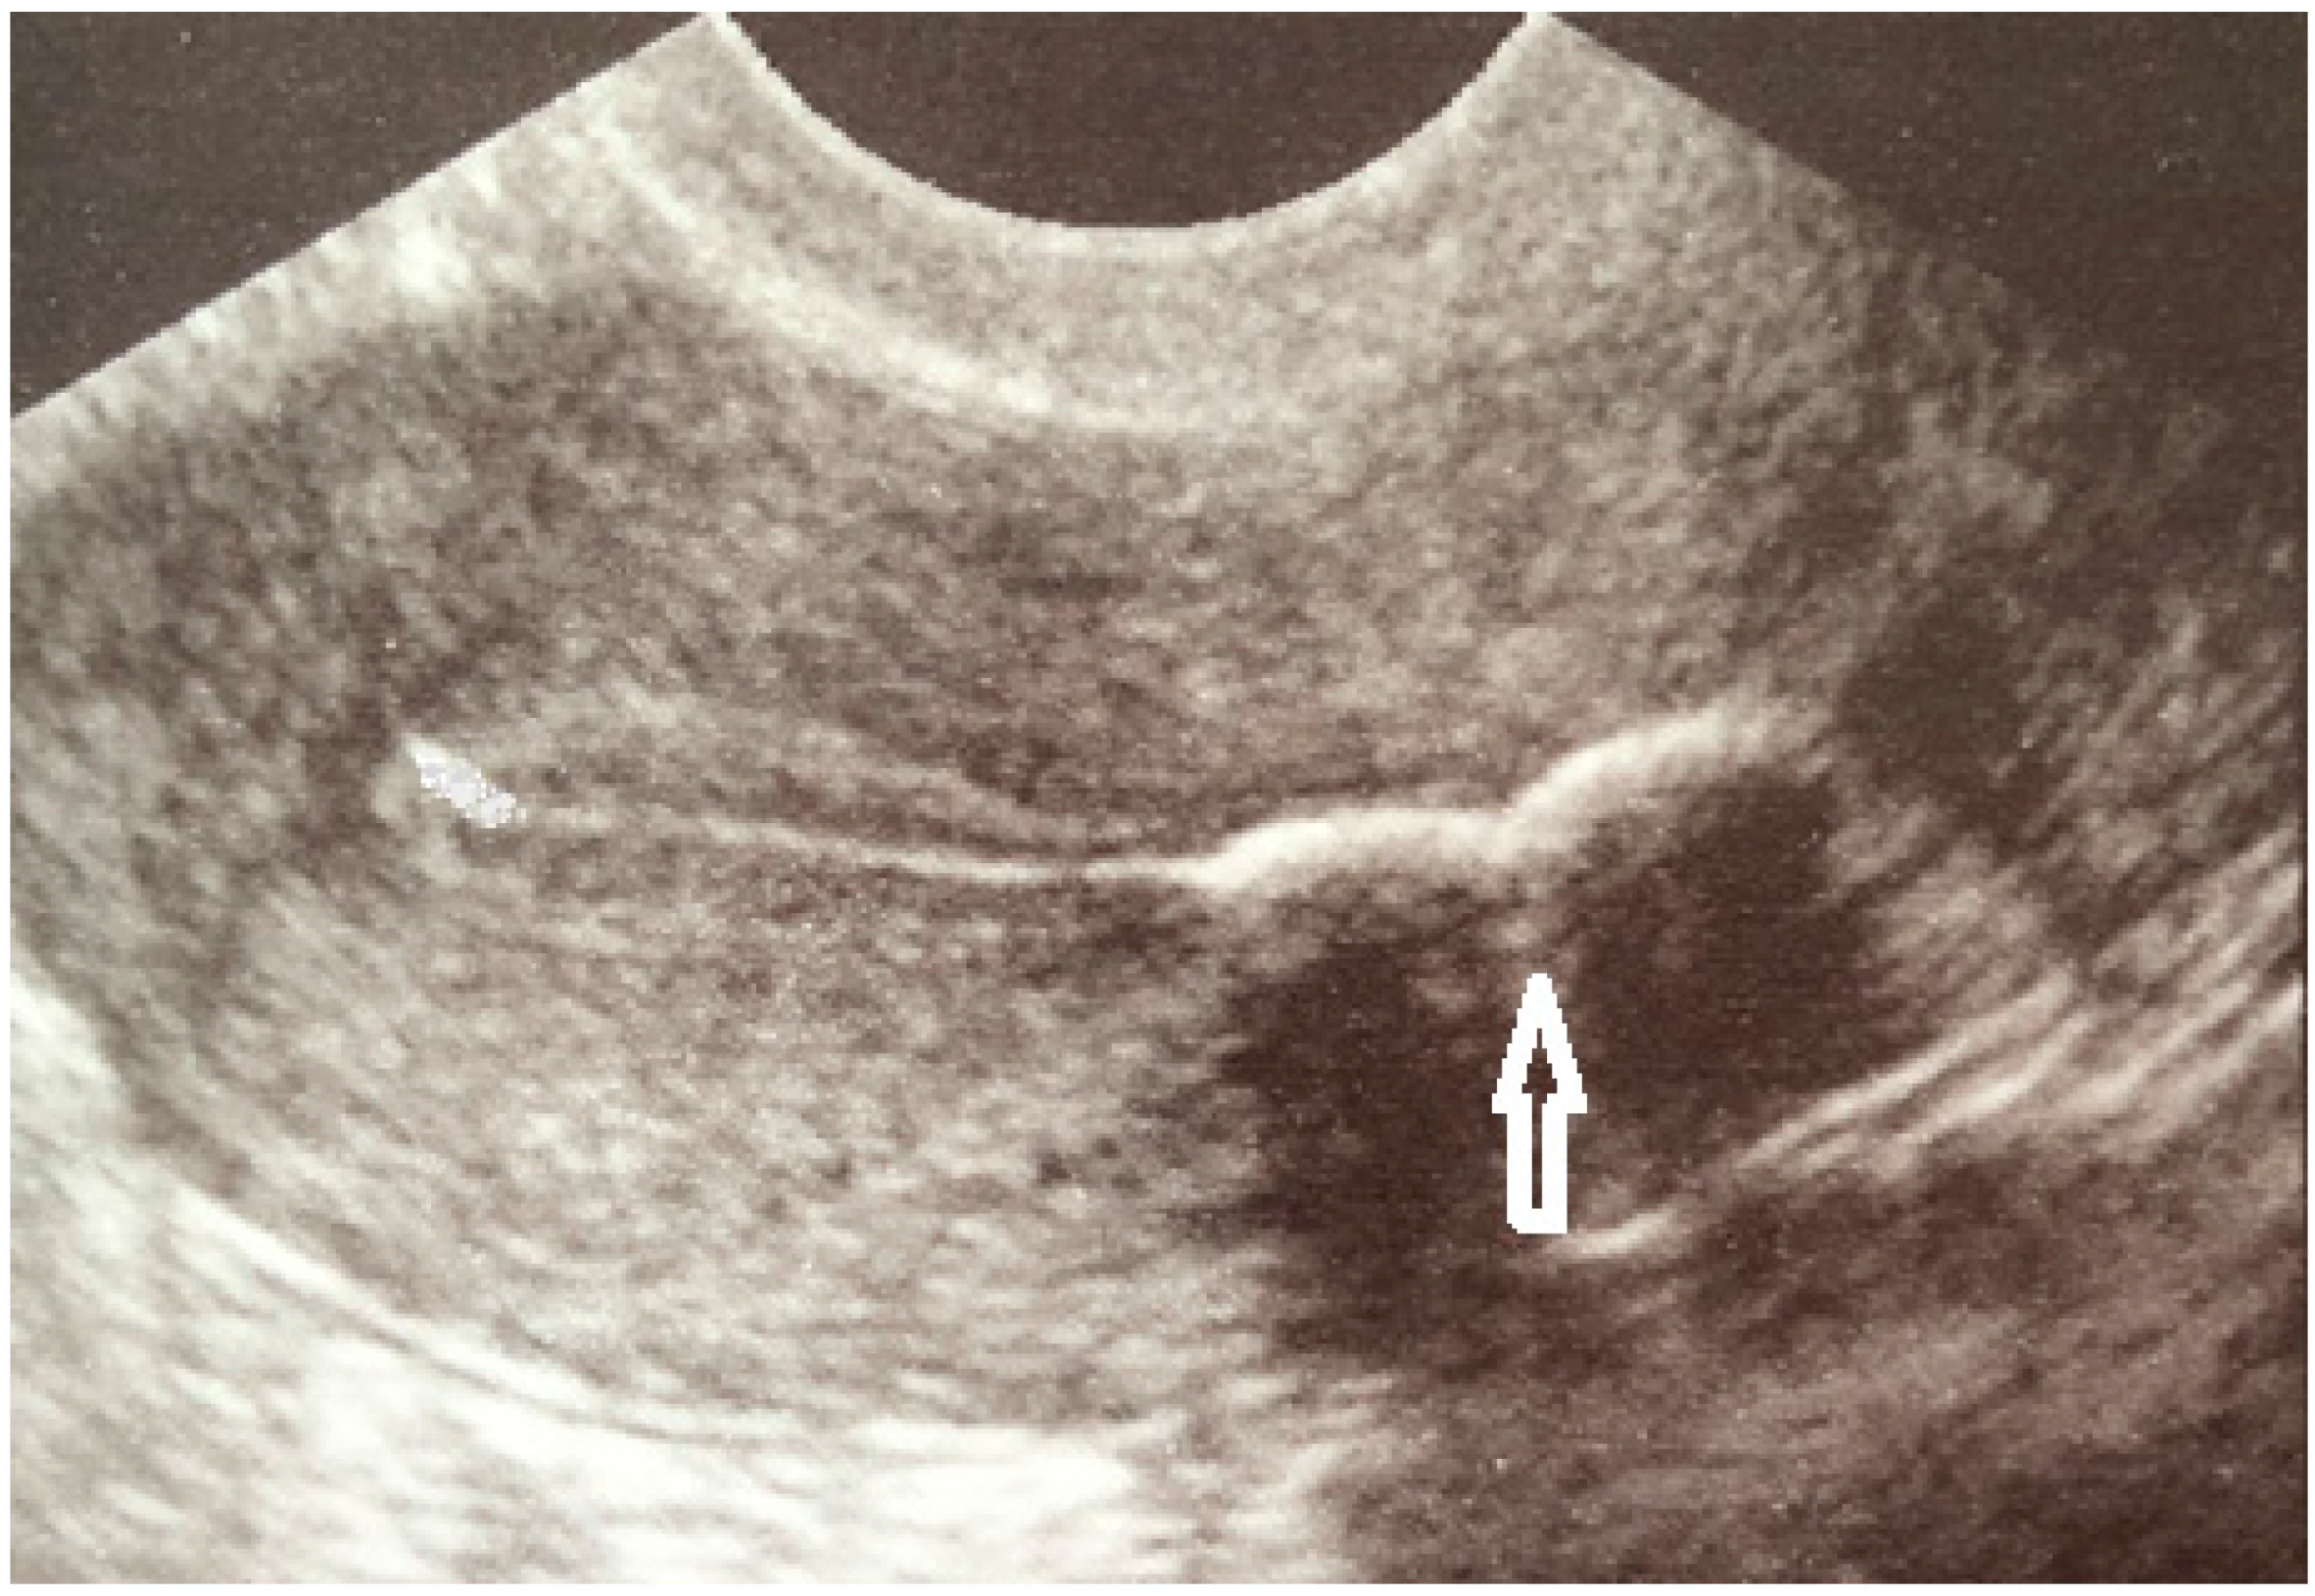

Case Report